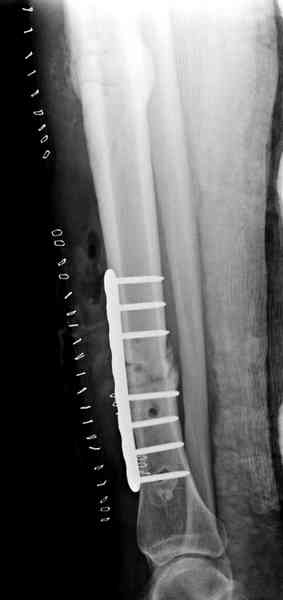

Недавно на нашей ежемесячной Morbidity&Mortality conference мы

разбирали похожий случай, ложный сустав большеберцовой кости после

резекции опухоли.

Оперирован в военном госпитале с заменой сегмента аллокостью

большеберцовой кости и после демобилизации явился для постоянного

наблюдения по месту жительства.

Наши имели проблему со сращением, пришлось им сделать динамизацию,

дополнительную аутопластику.

Имя     : 2 adamantioma lat preop.jpg